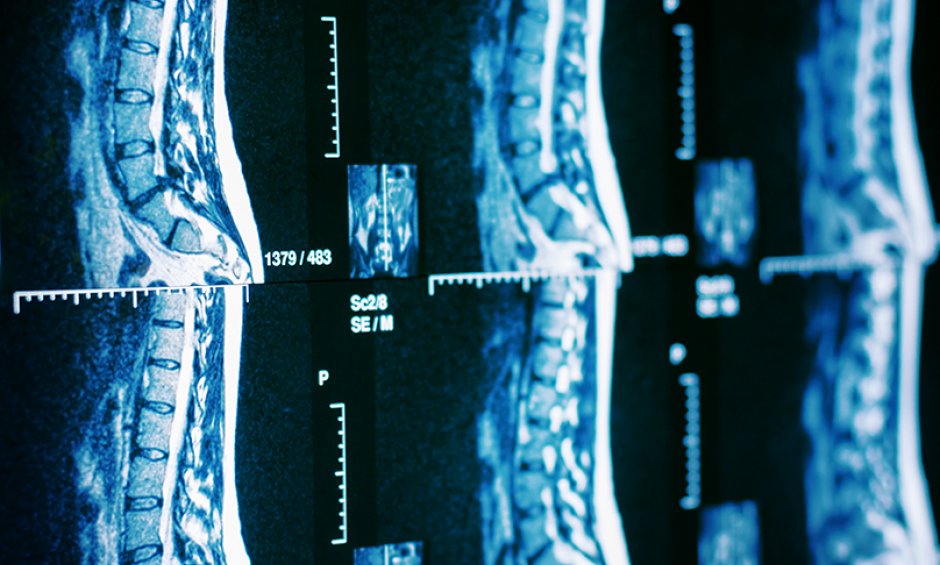

Το σχέδιο του χειρουργού στηρίζεται σε μια αξονική τομογραφία που γίνεται πριν ή κατά το χειρουργείο και φορτώνεται στον υπολογιστή του ρομπότ. Κατά τη διάρκεια της χειρουργικής επέμβασης, το ρομπότ διευκολύνει το σχέδιο επισημαίνοντας το σημείο εισαγωγής των εμφυτευμάτων.